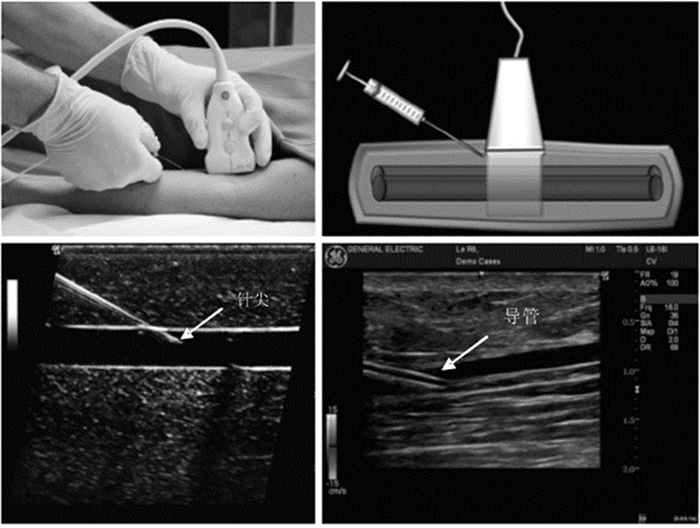

动静脉穿刺置管和浆膜腔穿刺是危重症治疗的常见技术。超声能够清晰地显示人体深部组织结构,并能对目标进行准确定位,同时还能实时观察目标的动态变化,避免严重并发症[41, 42, 43, 44],这使得超声引导穿刺技术应运而生。目前超声引导下穿刺技术已经广泛运用于临床,成为各种临床有创操作的安全保障。

3.6.2 介入操作的超声应用步骤及方法床旁超声引导下的介入操作基本原则包括:穿刺前常规进行超声检查,设计穿刺路径、测量穿刺深度等;选择合适的进针途径和最佳穿刺点,有效避免并发症。超声引导下穿刺,应选择评估合适的进针位置、深度;穿刺时超声引导,应降低显示深度,将穿刺针及针尖显示在屏幕上。

(1)超声引导血管穿刺 穿刺前首先应该在超声下识别目标血管,超声引导下血管穿刺有平面内(纵断面)和平面外(横断面)两种方法,它们各有特点,在实际操作中应该综合利用,互相补充。

平面内穿刺法(纵断面法)(图 40):是指超声探头长轴、血管长轴、穿刺针均位于同一平面内的超声引导穿刺方法。此种方法最大的优点是整个穿刺过程中穿刺针的全长及行进途径均始终显示在超声影像中,非常直观,全程可见,并发症少;其缺点主要是穿刺过程中容易丢失目标血管而误穿伴行的其他血管。

平面外穿刺法(横断面法)(图 41):是指超声探头长轴与血管长轴及穿刺针垂直的穿刺方法。此种方法穿刺针行;容易从血管壁正中穿入血管,减少血管侧壁损伤可能;穿刺过程中能始终监测伴行血管情况,避免误穿。其缺点是穿刺过程中仅能看见穿刺针的针尖(超声影像上表现为一后方伴有明显混响伪影的高回声亮点),无法看见穿刺针全程;针尖位置不易被识别,容易造成穿刺过深,穿透血管甚至损伤深层组织器。

超声探头多选择腹部探头。超声定位并标记腹腔穿刺点,一般选择“反麦氏点”或腹水最深处,且避开腹内脏器、如漂浮的肠管、膀胱、肝脾等。整个操作过程中都在超声引导下进行。针尖及导丝一旦进入无回声的液体区时就可表现为强回声影(图 44)。

|

| 图 44 腹水中漂浮的肠袢(左上),箭头所示;穿刺针尖(右上);置入导丝(左下);置入导管(右下) |